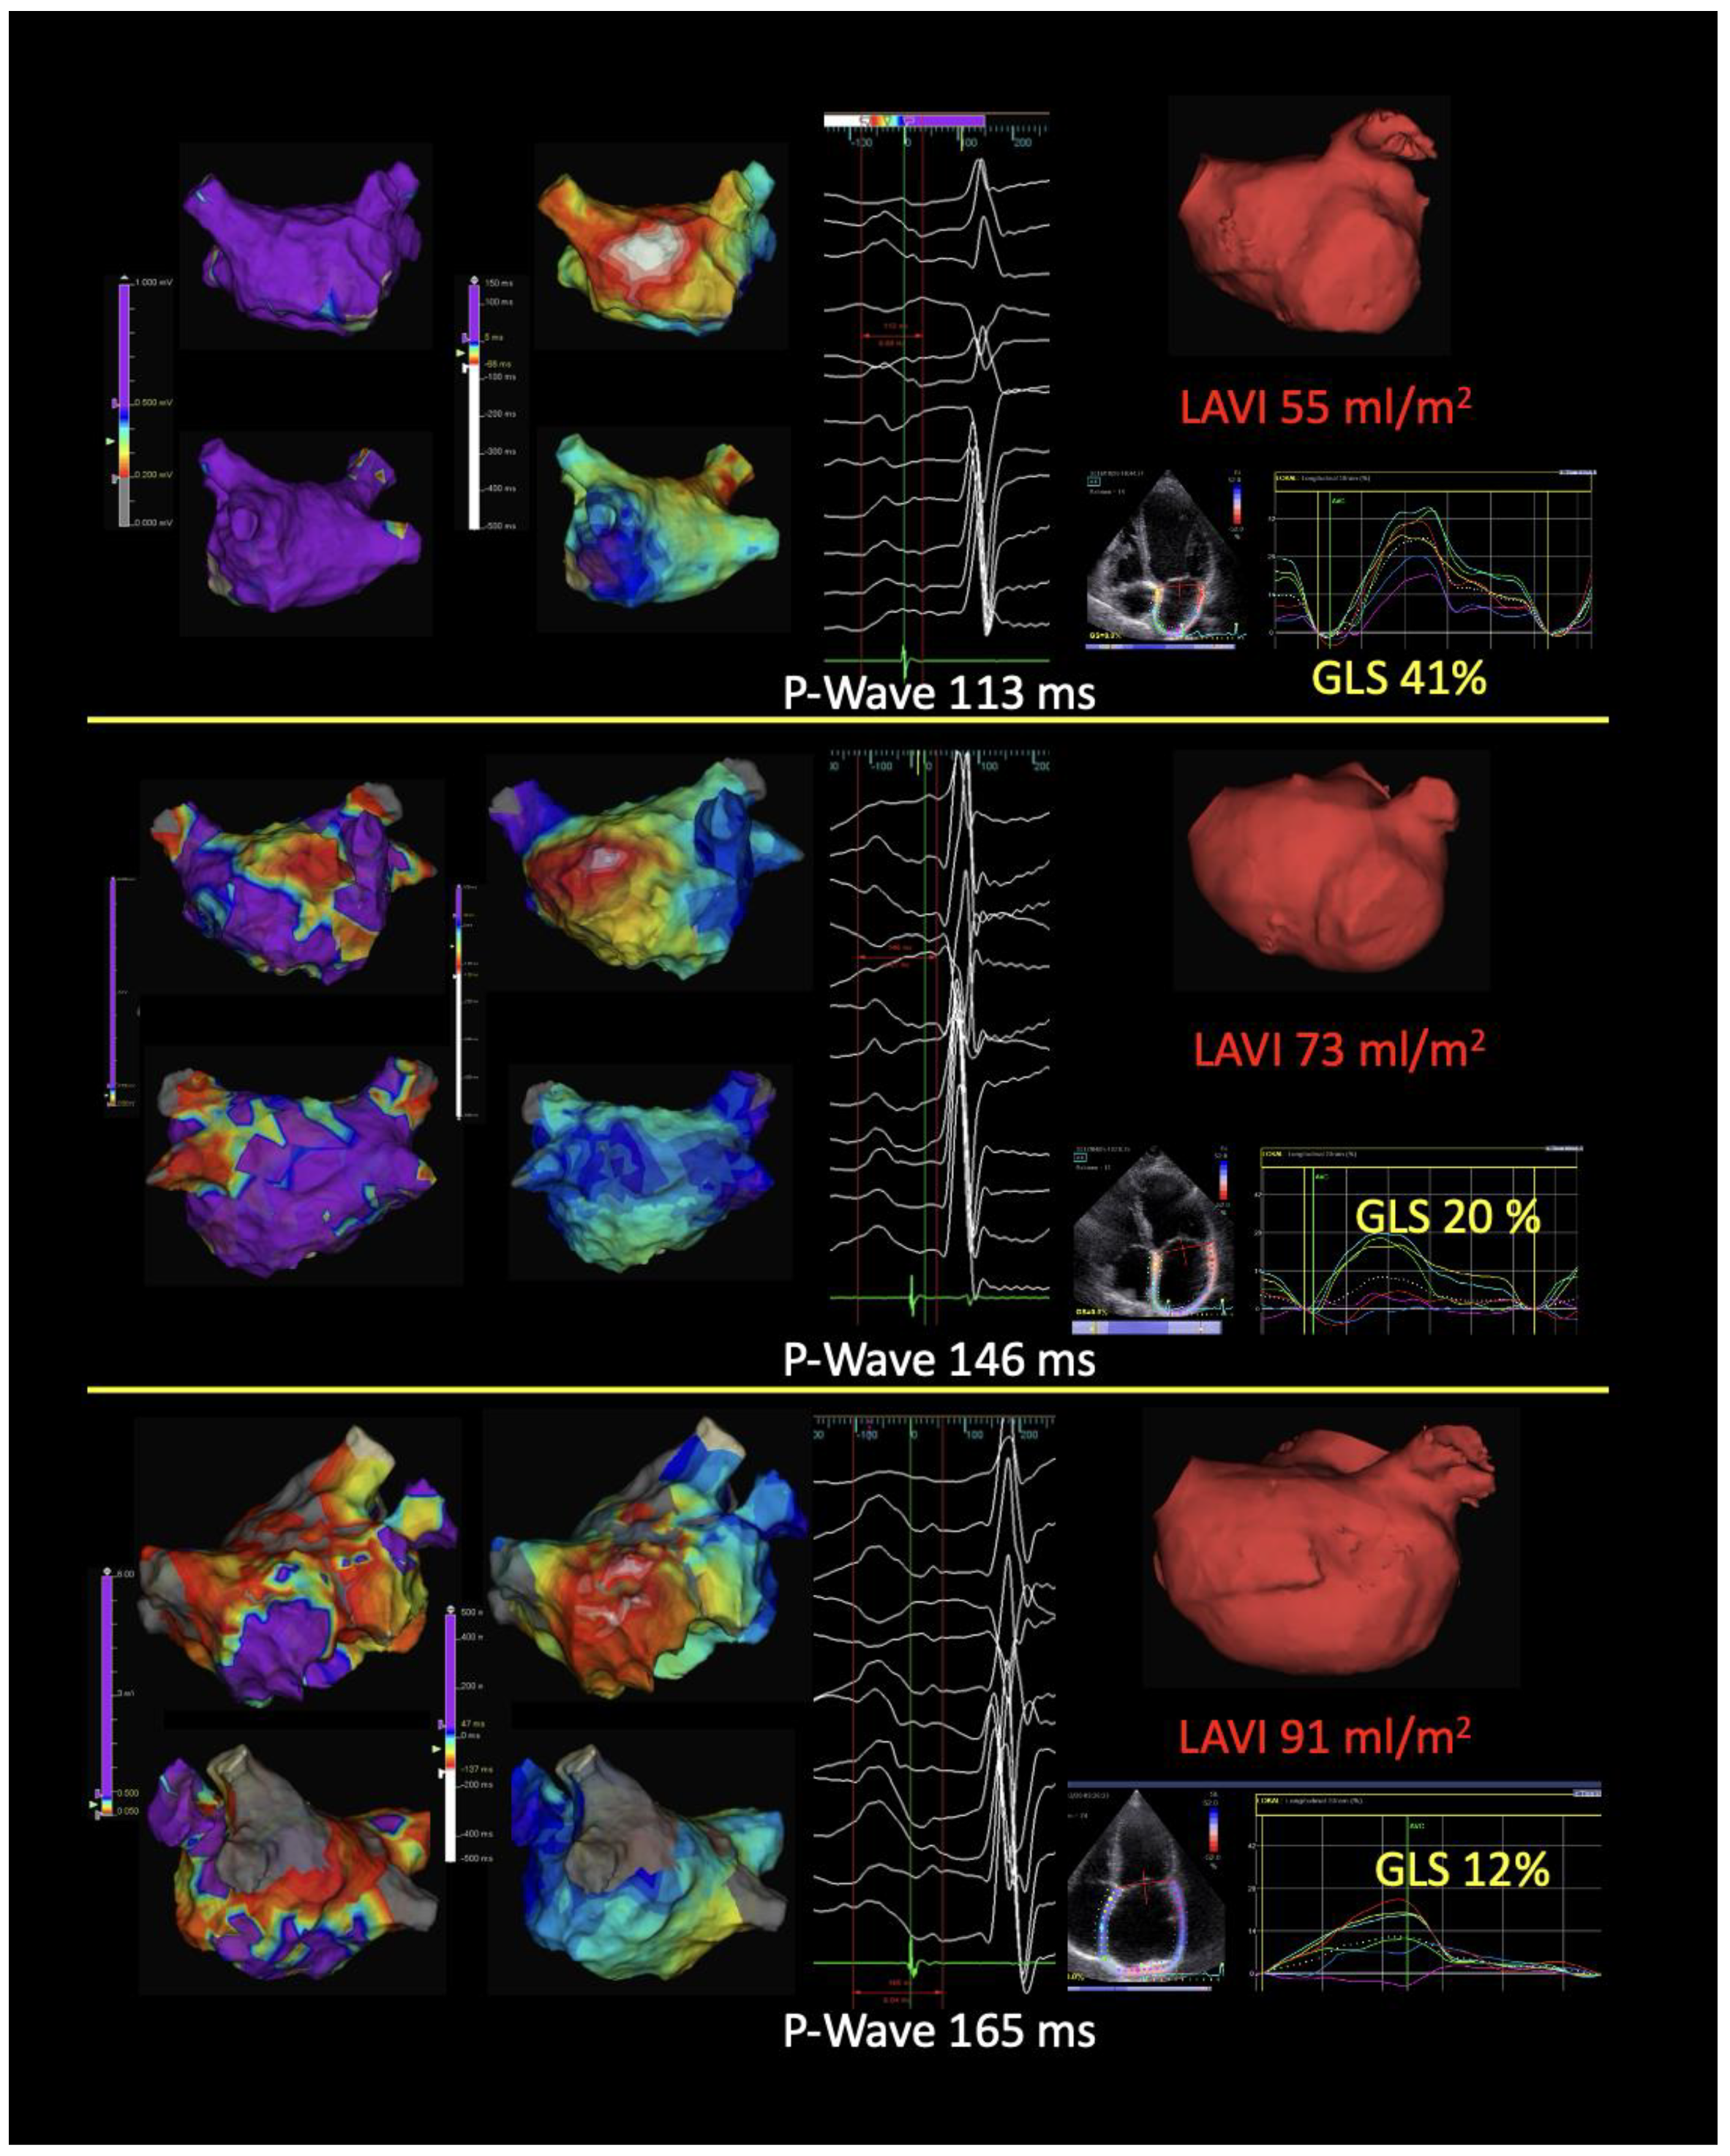

4. Atrial Cardiomyopathy and the Role of Imaging in Risk Stratification

- Goette, A.; Corradi, D.; Dobrev, D.; Aguinaga, L.; Cabrera, J.-A.; Chugh, S.S.; de Groot, J.R.; Soulat-Dufour, L.; Fenelon, G.; Hatem, S.N.; et al. Atrial Cardiomyopathy Revisited—Evolution of a Concept: A Clinical Consensus Statement of the European Heart Rhythm Association (EHRA) of the ESC, the Heart Rhythm Society (HRS), the Asian Pacific Heart Rhythm Society (APHRS), and the Latin American Heart Rhythm Society (LAHRS). Europace 2024, 26, euae204. [Google Scholar] [CrossRef]

- Hauser, R.; Nielsen, A.B.; Skaarup, K.G.; Lassen, M.C.H.; Duus, L.S.; Johansen, N.D.; Sengeløv, M.; Marott, J.L.; Jensen, G.; Schnohr, P.; et al. Left Atrial Strain Predicts Incident Atrial Fibrillation in the General Population: The Copenhagen City Heart Study. Eur. Heart J. Cardiovasc. Imaging 2021, 23, 52–60. [Google Scholar] [CrossRef]

- Serenelli, M.; Cantone, A.; Dal Passo, B.; Di Ienno, L.; Fiorio, A.; Pavasini, R.; Passarini, G.; Bertini, M.; Campo, G. Atrial Longitudinal Strain Predicts New-Onset Atrial Fibrillation. JACC Cardiovasc. Imaging 2023, 16, 392–395. [Google Scholar] [CrossRef]